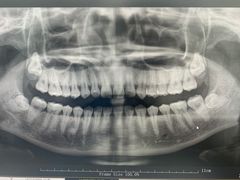

• 牙博士口腔品牌连锁(杨浦店)

• -牙博士口腔品牌连锁(杨浦店)

pudding蕊_4175 | 20-12-27

报错